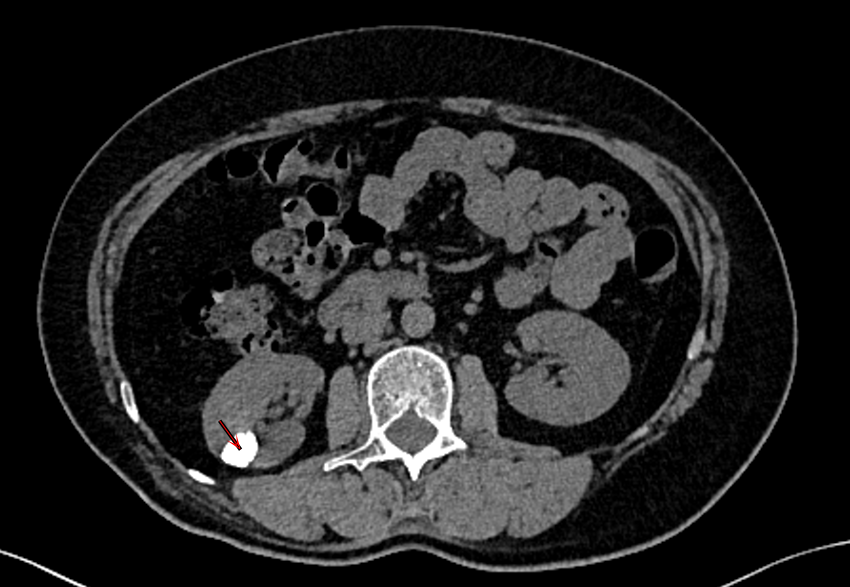

一位来自江苏徐州刚刚退休的吴女士,被突如其来的腰痛和血尿扰乱了正常生活。经朋友介绍,吴女士来到了苏州大学附属第四医院(苏州市独墅湖医院)泌尿外科周守军主任医师的门诊。在完善腹部CT检查后发现,吴女士的右肾内多发结石,最大直径有2cm。结石对于吴女士来说并不陌生,15年前她就因右肾结石,在老家做了“肾实质切开取石术”,术后这些年也断断续续有小结石自行排出。

周主任仔细阅片后,发现吴女士的结石并不简单。患者除了肾盏内一些多发的结石,还有一颗最大的结石位于肾盏憩室内,且非常靠近肾实质边缘,这正是引起腰痛和血尿的罪魁祸首。肾盏憩室是肾实质内的一个腔体,与肾盂、肾盏之间经过狭窄的通道相通,而这一憩室很有可能是吴女士15年前肾脏手术造成的。周主任在了解吴女士想一次性清除肾脏内所有结石的诉求后,决定收住入院,同时拟定安全可靠且清石率高的手术方式。